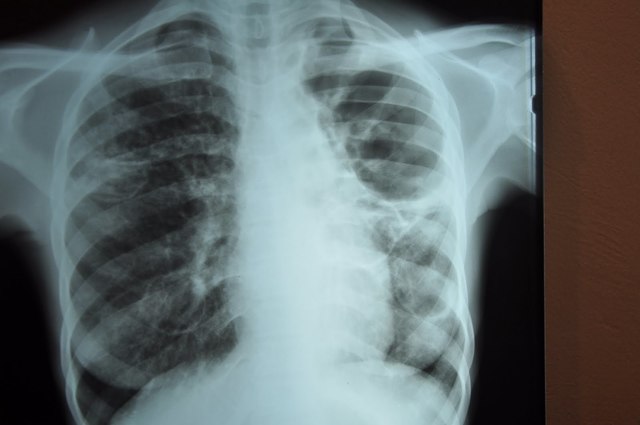

• Discovery of X-Rays

Discovery of X-Ray use aided in tuberculosisidentification